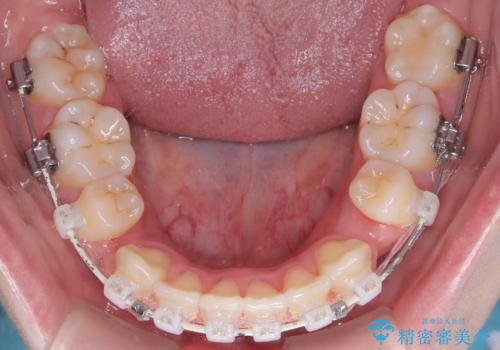

- 矯正装置

- 審美ワイヤー装置

- 患者様は、結婚式までに歯並びを整えたいとのご要望で来院されました。診断の結果、上下左右の第一小臼歯を抜歯し、歯列全体を整える計画としました。審美性を重視し、目立ちにくいホワイトワイヤーを使用した矯正を提案しました。治療期間は2年を目安とし、結婚式までに前歯の整列と噛み合わせを優先的に整えるスケジュールで進めました。定期的な調整と経過観察を通じて、計画的に治療を進めました。

結婚式までに仕上げるため、通常よりも細かく調整を行い、歯の動きを効率的に管理しました。審美ワイヤーを使用したことで、治療中も目立ちにくく、写真撮影などの日常生活での見た目の負担を軽減しました。抜歯部分のスペースを閉じる際には、前歯の位置や噛み合わせのバランスに配慮し、過度な力がかからないよう進めました。患者様の大切なイベントに間に合うよう治療計画を立て、理想的な仕上がりを実現しました。